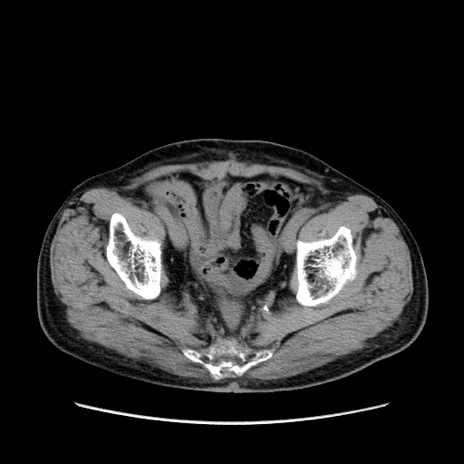

症例24(横断像)

【症例】80歳代男性

【主訴】左側腹部痛、嘔吐

【現病歴】本日早朝より左腹部に痛みあり。昼頃嘔吐認めたため、救急要請。

【既往歴】直腸癌(Mile手術)、胆摘

【身体所見】意識清明、BT 35.9℃、BP 221/93mmHg、SpO2 97%(RA) 、腹部:左ストーマ周囲に限局性の腹部膨隆あり。 膨隆部自発痛・圧痛あり・軟。

【データ】WBC 7700、CRP 0.09